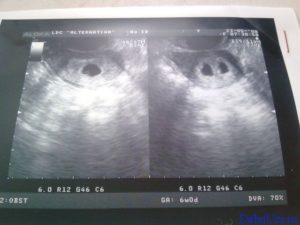

Узи двойни при беременности: фото на ранних сроках в 5-6 недель и позже

Следовательно, наличие двойняшек в утробе выявляется посредством ультразвука уже через месяц после зачатия, на снимке они выглядят как 2 образования темного цвета внутри полости матки (см. фото УЗИ-обследования двойни ниже).

Если беременность содержит однояйцевых близнецов, то обнаружить их можно исключительно на 12 неделе и не ранее.

Считается, что точно увидеть несколько эмбрионов, можно только при помощи УЗИ. На каком сроке определяют многоплодную беременность? Специалист может увидеть данный факт в 5-6 недель. Но, как правило, ее диагностируют во время первого скрининга в 12 недель.